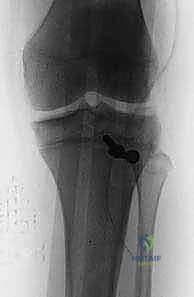

2. التصوير بالأشعة السينية (X-Rays)

هو الخطوة التشخيصية الأساسية. يتم أخذ صور من زوايا متعددة (أمامية خلفية AP، وجانبية Lateral). الصورة الجانبية هي الأكثر أهمية لأنها تظهر بوضوح مدى انفصال (انزياح) حدبة الظنبوب عن مكانها الطبيعي، وتظهر أيضاً ارتفاع الرضفة (Patella Alta).